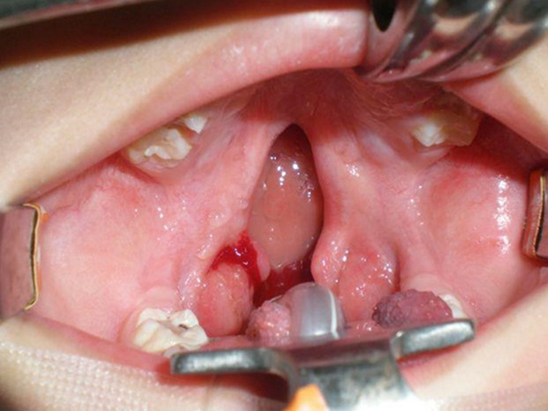

Cleft lip and/or cleft palate

Cleft lip and/or palate